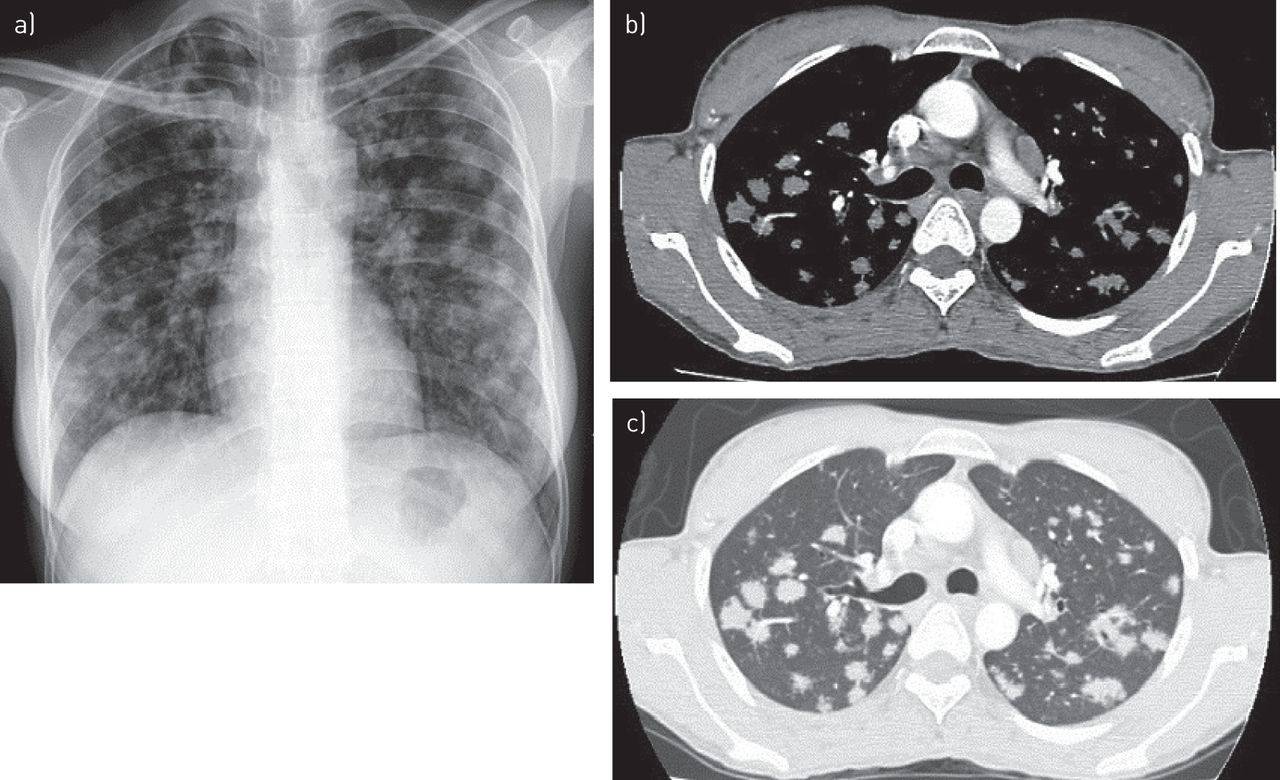

КТ легких не показывает конкретного возбудителя туберкулезной инфекции из класса микобактерий, однако показывает изменения в легких которые не видны на обычном рентгене или флюорографии из-за сравнительно низкой разрешающей способности последних, неполного обзора, эффекта наложения теней, который искажает результаты диагностики.

По специфической КТ-картине рентгенологи определяют следующие виды туберкулеза:

- Милиарный туберкулез (синдром милиарной диссеминации) — характеризуется наличием множественных просовидных бугорков в легких, расположенных сравнительно равномерно.

- Диссеминированный туберкулез легких —множественные очаги туберкулеза в обоих легких имеют разную величину и расположены диффузно.

- Очаговый туберкулез —характеризуется наличием одиночных или множественных очагов до 1 см в диаметре. Если очагов несколько, то расположены они в одном месте.

- Инфильтративный туберкулез легких —характеризуется наличием бронхо-пневмонического воспаления, формирования участка инфильтрации легочной ткани, более 1 см в диаметре.

- Кавернозный туберкулез легких —характеризуется формированием полости деструкции, распада легочной ткани в следствии запущенного инфекционного процесса, так называемой каверны круглой или овальной формы.

- Фиброзно-кавернозный туберкулез —наряду с кавернами в легких присутствуют признаки фиброза, который является агрессивной ответной реакцией организма на воспаление и деформирует матрикс легкого в легких формируются туберкулезные рубцы).

Первичный туберкулезный комплекс (ранняя стадия заболевания) характеризуется наличием очага или их группы в легких, увеличением лимфоузлов. На КТ с одной или, чаще всего с обеих сторон в долях легких визуализируются уплотнения – сравнительно более светлого цвета, чем вся легочная паренхима, имеют специфическую, отличную от легочного матрикса, сосудов и бронхов форму.

Ежегодная профилактическая флюорография — быстрое, доступное и, безусловно, полезное обследование. Но данный рентгенографический метод, изобретенный в первой половине XX века с наибольшей вероятностью покажет туберкулез «в общем» и на более поздних стадиях. Поэтому более предпочтительным методом диагностики туберкулеза сегодня считается скрининговая низкодозная КТ легких (МСКТ легких).